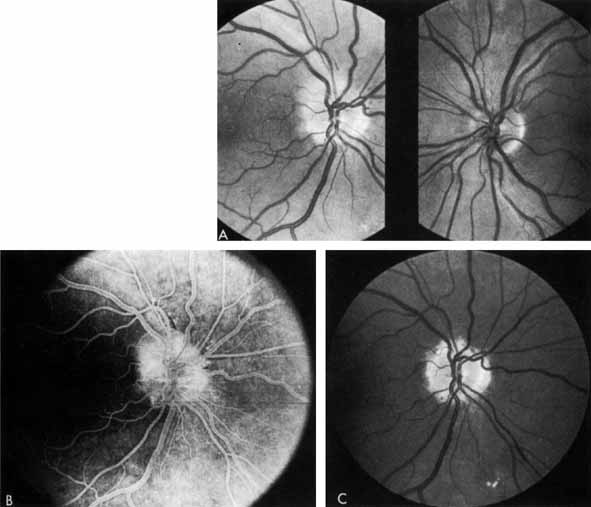

As demonstrated by increased latency and decreased amplitude of the visual evoked potential, many patients with diabetes without retinopathy have subclinical optic neuropathy.269,270 In addition, patients with diabetes can develop two types of acute optic neuropathy. The first, anterior ischemic optic neuropathy (AION) is identical to that seen in patients without diabetes. The patients report a sudden decrease in visual acuity or a sudden visual field loss.271–273 The main ocular finding is a “pale swelling” of the optic nerve head with, considering the degree of disc edema, very few hemorrhages (Fig. 27). On fluorescein angiography segmental nonfilling or slow filling is seen (Fig. 27). An afferent pupillary defect (Marcus Gunn) is nearly always present. Visual fields commonly show altitudinal or nerve fiber bundle defects. The disc progresses to optic atrophy (Fig. 27), and improvement in visual function is rare.

Fig. 27 A. Right eye: ischemic optic neuritis. Note pale swelling of optic disc and blurring of disc margins. Left eye: normal disc. B. Fluorescein angiogram. Note poor filling on disc inferotemporally as compared with the rest of the disc. C. Right eye 6 months after optic neuritis. Note slight pallor.

The other type of acute optic neuropathy, commonly called diabetic papillopathy, is characterized by acute disc edema without the pale swelling of AION. It is bilateral in one-half of cases. The vision usually recovers to better than 20/50 with or without an afferent pupillary defect.274 Macular edema is a common finding and is the most common cause of failure of visual recovery.274 Visual fields may be normal, show an increased blind spot, or have disc-related defects. The prognosis is excellent as nearly all patients recover to 20/30 or better.275–277